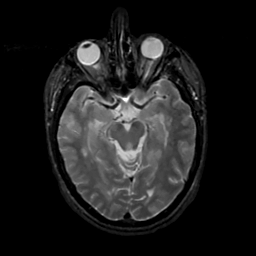

MR Study #8, March 31, 1991 -- Slice #20